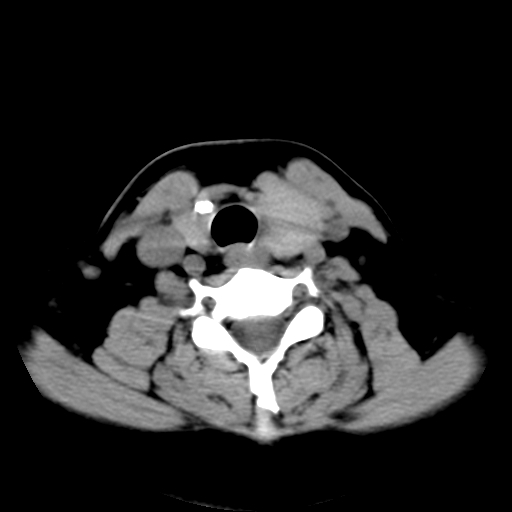

标题: CT25491:女,55岁,发现左侧甲状腺肿块一个月。 [打印本页]

女,55岁,发现左侧甲状腺肿块一个月,彩超示:甲状腺多发结节伴左叶结节液化。

考虑左侧甲状腺结节性甲状腺肿,不排除甲状腺腺瘤。